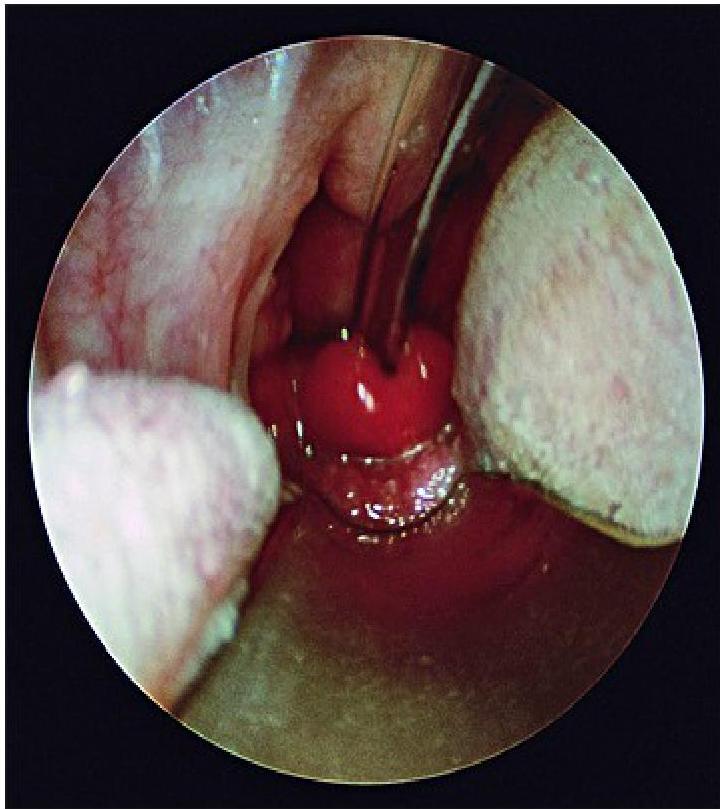

- Direct Visualization: Preferred if clinical suspicion is high. Performed during airway management in the operating suite. Shows a swollen, cherry-red epiglottis with an endotracheal tube passing posteriorly.

swollen cherry-red epiglottitis with an endotracheal tube passing posteriorly